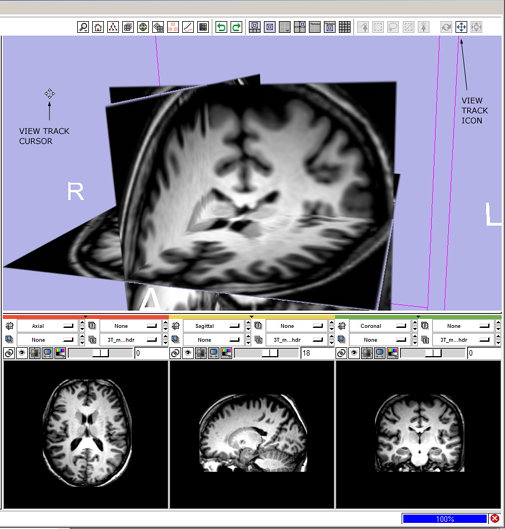

3(novice) track: click the view track mouse-mode icon ![]()

- --> mouse-track icon highlights and all others deselect, cursor changes to indicate mouse-track mode.

- then left-Click and drag in the 3D Viewer to translate the view left-right, and up-down,

3(expert) track: alt+left-Click and drag in the 3D Viewer,

- --> mouse-track icon

highlights and all others deselect; cursor changes to indicate mouse-track mode; view tracks.

highlights and all others deselect; cursor changes to indicate mouse-track mode; view tracks.